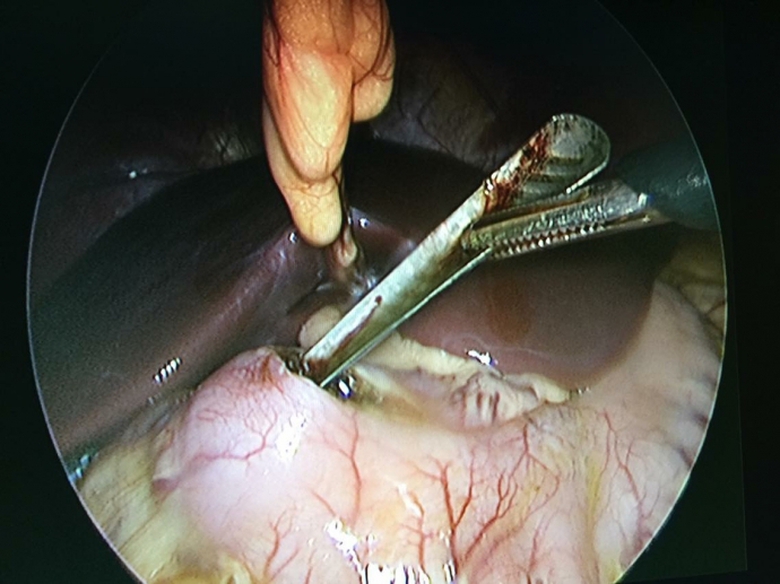

Bệnh viện Trung ương Huế lấy thìa bằng cách nội soi ổ bụng. Ảnh: Bệnh viện Trung ương Huế |

Ê kíp mổ của Khoa Ngoại nhi - Cấp cứu bụng (Bệnh viện Trung ương Huế), gồm TS. Phan Hải Thanh, Th.s. Phạm Xuân Đông, BS. Gây mê Nguyễn Trung Hậu lấy dị vật ra bằng nội soi ổ bụng.

Các bác sĩ đã mở lỗ nhỏ ở hang vị dạ dày rồi dùng dụng cụ nội soi lấy dị vật từ đoạn D2 tá tràng. Sau khi được lấy dị vật bằng nội soi ổ bụng, tình trạng sức khỏe bệnh nhân Hà đã ổn định và chờ ngày xuất viện.